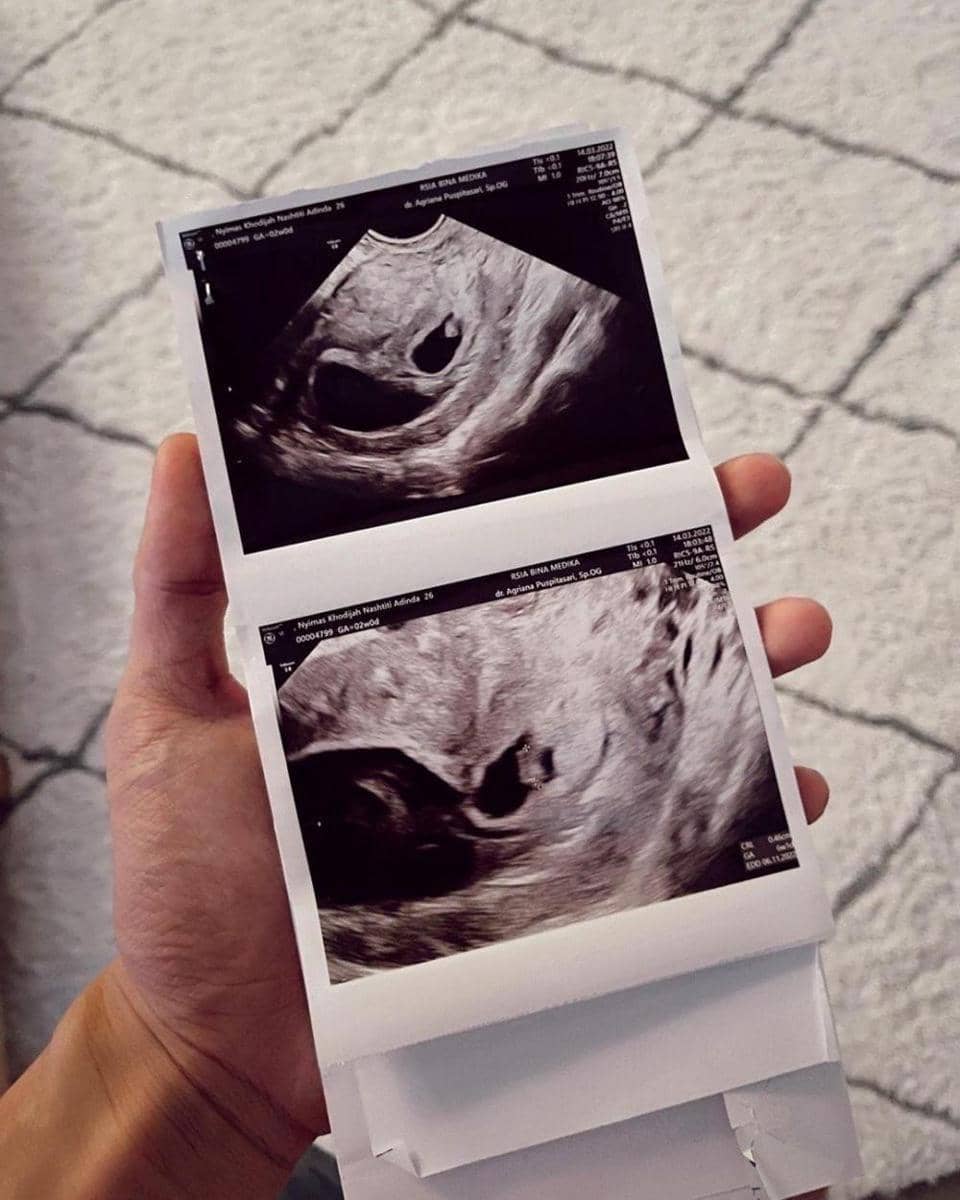

2. Setelah melakukan tes kehamilan, Dinda langsung pergi ke dokter kandungan untuk USG. Dokter menjelaskan ada bayi kembar dalam kandungannya.

3. Namun, dokter menjelaskan bahwa salah satu kantung rahimnya ada janinnya, tapi yang satu lagi tidak berkembang. Mendengar hal itu, Dinda dan Rey hanya bisa pasrah dan berdoa.